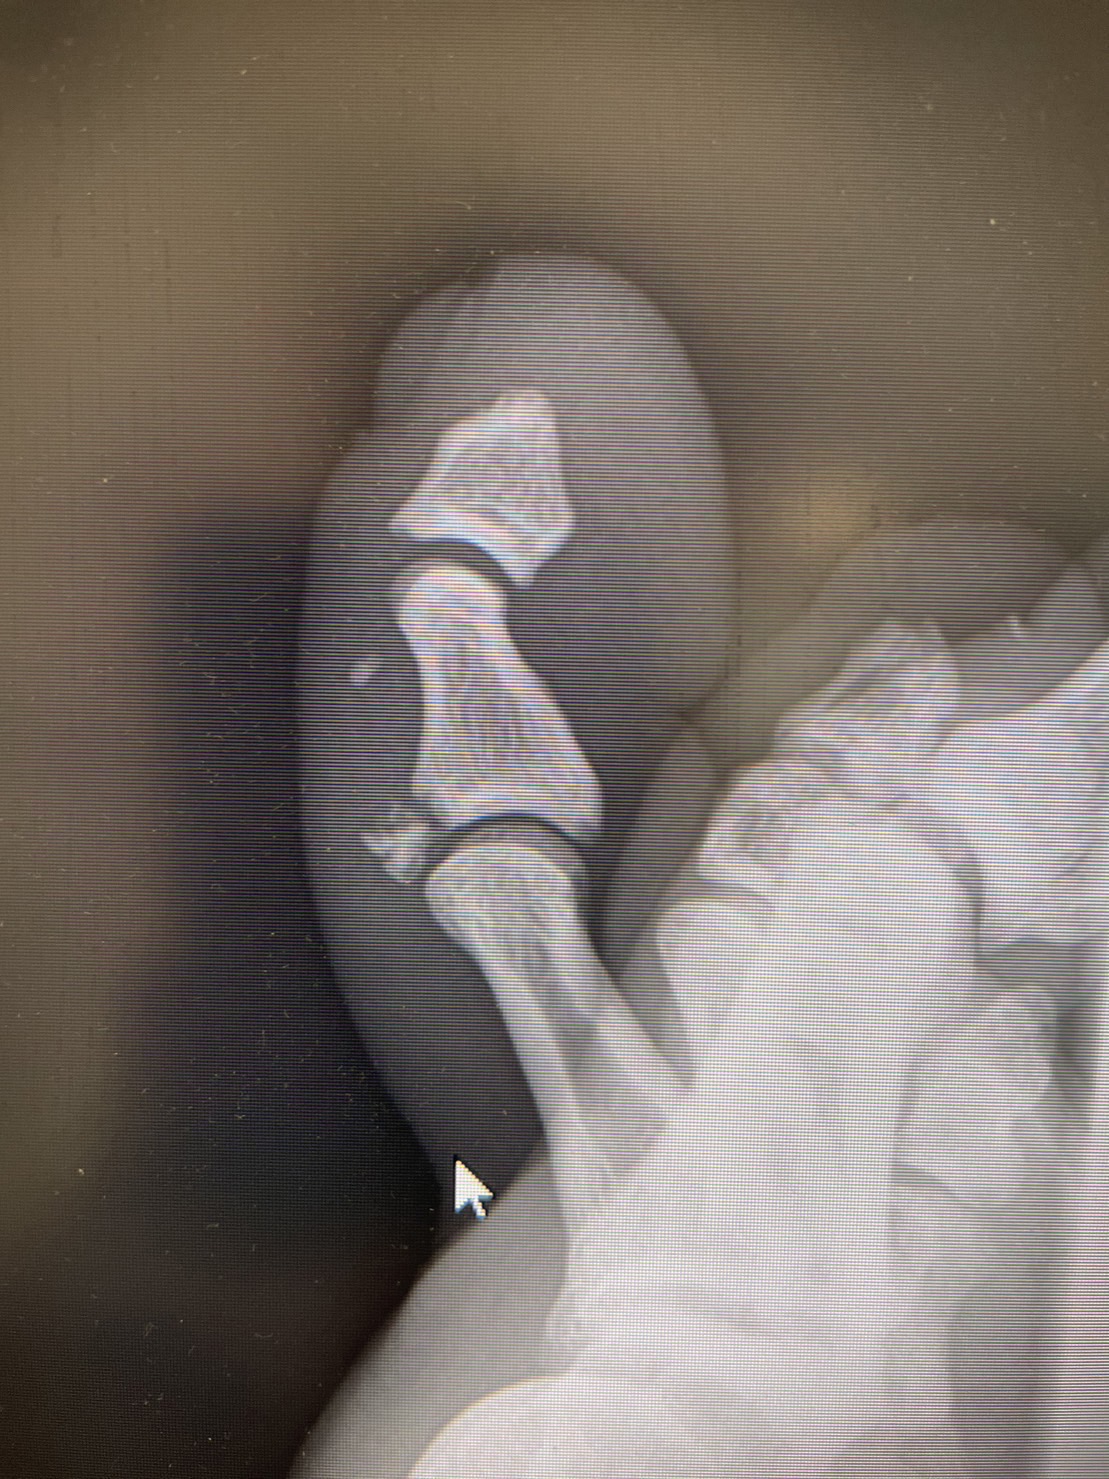

3月26日の『RISE ELDORADO 2023』でRISEミドル級タイトルを獲得した海人は、翌日の一夜明け会見に出席して大阪に戻って昨日、若干左足に痛みがあったことから念のため病院で検査を受けたところ「左第2趾中節骨伸筋腱付着部剥離骨折」と診断された。